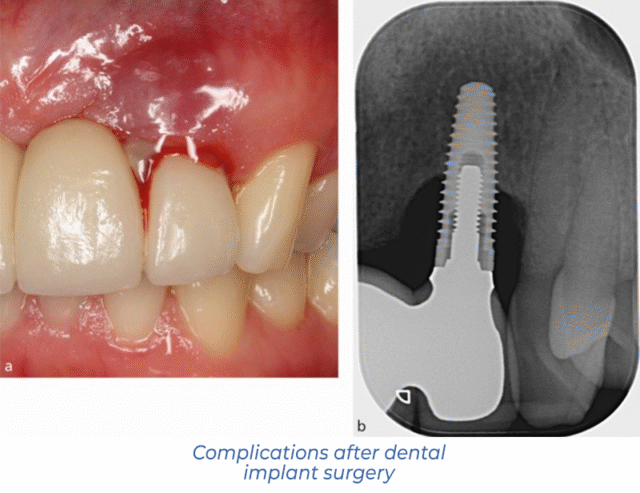

How do I know if an implant has failed?

Signs of dental implant failure can occur at different times, from a few months to several years after surgery. Suppose the problems are caused by medical errors or non-compliance with the rehabilitation rules. In that case, they usually manifest themselves in the first weeks after implant surgery. Symptoms of poor implant engraftment include:

- severe pain in the area of surgical intervention;

- significant swelling of the gum and cheek on the implant side;

- redness or lividity of the mucous membrane around the implant;

- purulent, oozing or bloody discharge from under the gingiva;

- bad, putrid breath odour;

- mobility of the implant;

- increased body temperature, weakness and other general signs of malaise.

Do not forget that soreness, swelling, and slight bleeding are natural reactions after surgical manipulation. Normally, they pass in 3-5 days and do not significantly affect the patient’s quality of life. If such symptoms last longer than 5-7 days and increase over time, they indicate postoperative complications.

Diagnosis: CT scan, X-ray, examination

For successful treatment, the dentist must understand why the dental implant has not fused. The doctor begins the appointment by clarifying the patient’s complaints and examining the oral cavity, during which he assesses local signs of inflammation.

Next, they will refer the patient for dental X-rays or a high-precision CT scan. The resulting images show the condition of the tissues around the tooth implant and allow for a correct diagnosis.